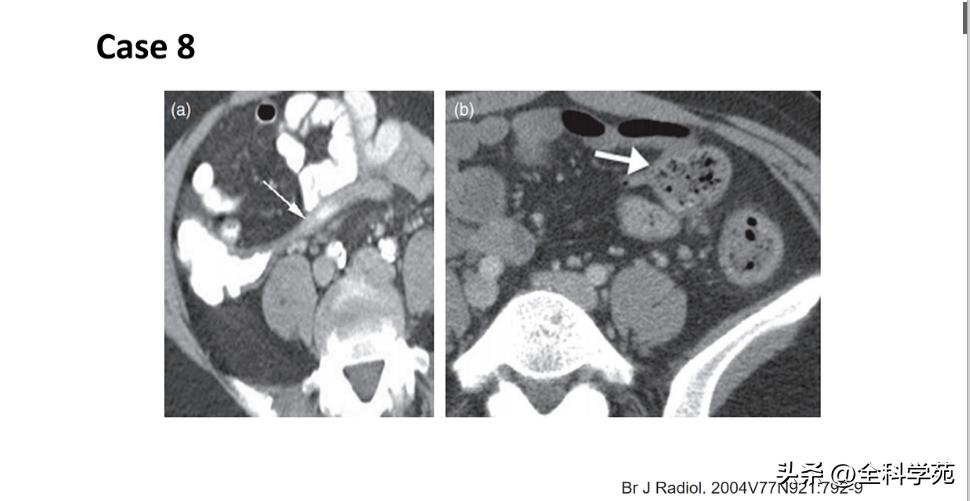

◆ 门静脉炎 (Pylephlebitis)